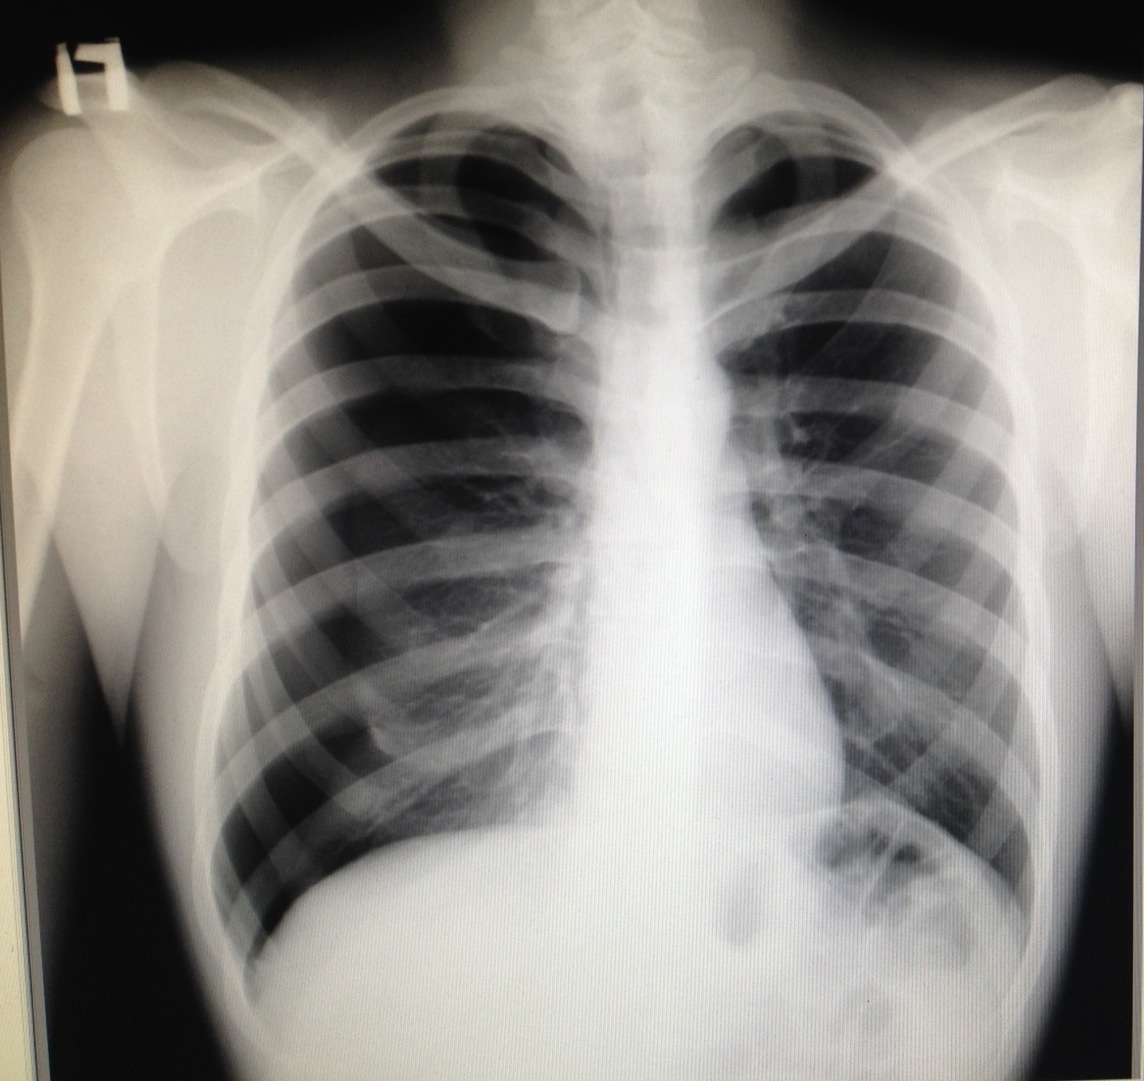

Проведена рентгенография органов грудной клетки в прямой проекции, положение полусидя, условия ПИТ, Р-контроль Легочные поля: Отрицательная динамика: правое легкое поджато к корню. Тень средостения резко смещена влево. Выраженная подкожная эмфизема мягких тканей грудной клетки справа. Тень подключичного катетера в проекции ВПВ. Легочный рисунок: диффузно деформирован за счет пневмосклероза, сгущен справа Корни: тень средостения смещена влево Синусы: нечеткие Сердце: широко лежит на диафрагме (позиционно) ЗАКЛЮЧЕНИЕ: Правосторонний пневмоторакс, отрицательная Р-динамика. Эмфизема мягких тканей грудной клетки. Пневмосклероз. Р-контроль.